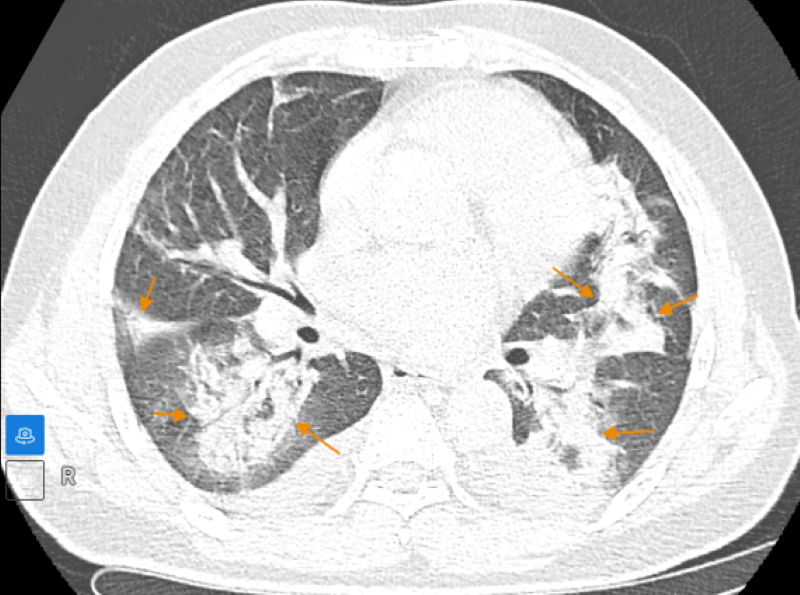

Trên hình ảnh chụp cắt lớp vi tính (CLVT) phổi cho thấy tổn thương đông đặc nhu mô phổi, kèm theo xẹp phổi quanh bó mạch - phế quản. Dày tổ chức kẽ dạng lưới và các vùng kính mờ tập trung thành đám, lan tỏa trong nhu mô phổi, tràn dịch khoang màng phổi hai bên.

Phim chụp cắt lớp vi tính phát hiện tổn thương đông đặc nhu mô phổi